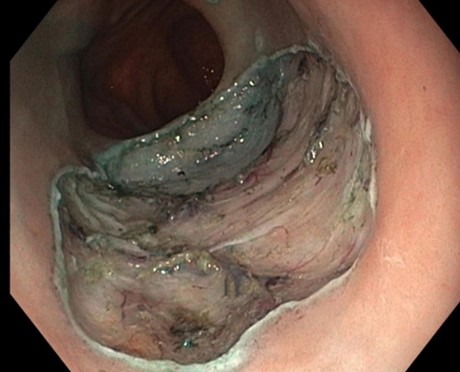

Anschließend wurde der ausgeschaltete Magen mit Flüssigkeit gefüllt und eine Verbindung zwischen dem kleinen Magenrest und dem ausgeschalteten Magen geschaffen (Abbildung 2).

Diese Verbindung wurde mithilfe eines speziellen Metallstents (LAMS, „Hot Axios“) angelegt. Da bei der Patientin keine akute Entzündung der Gallenwege bestand, konnte einige Tage abgewartet werden, bis sich der Stent vollständig entfaltet hatte. Über diesen neu geschaffenen Zugang war es anschließend möglich, die notwendige ERCP durchzuführen und die Gallensteine zu entfernen (Abbildung 3).